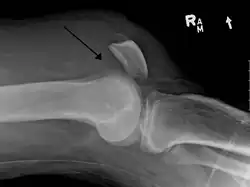

Quadriceps tendon rupture in plain X-ray: Incomplete rupture with haematoma in tendon. -